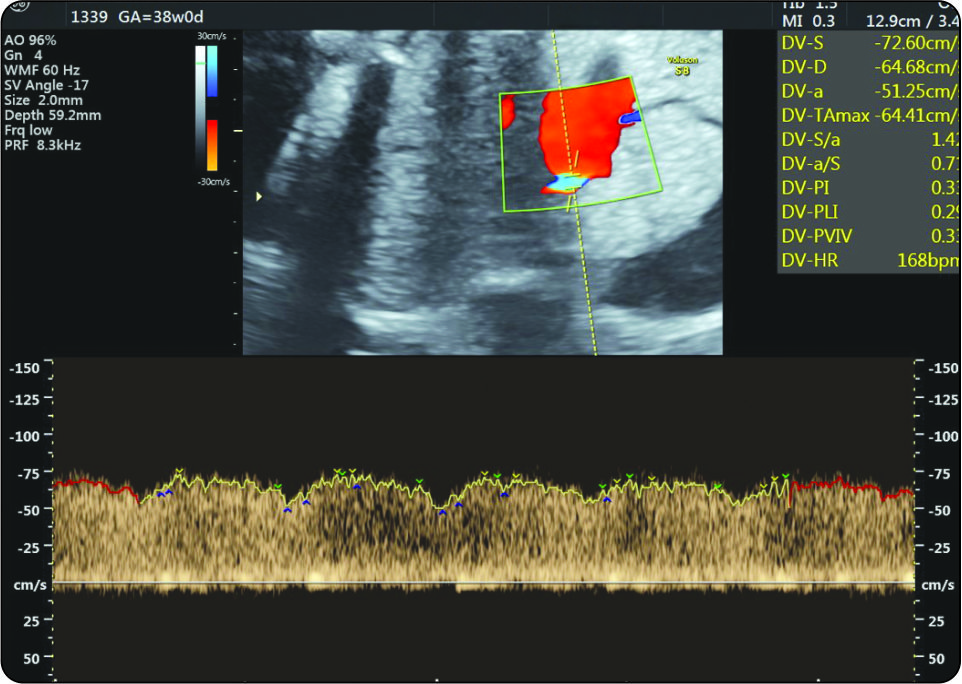

Umbilical Coiling Index: An Important Predictor of Fetal Outcome

Aruna Nigam, Anshu Sharma, Arifa A Elahi, Swaraj Batra

page 44-47

Full text PDF